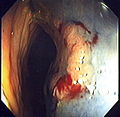

An advantage of colonoscopy over X-ray imaging or other less invasive tests is the ability to perform therapeutic interventions during the test. A polyp is a growth of excess of tissue that can develop into cancer. If a polyp is found, for example, it can be removed by one of several techniques. A snare device can be placed around a polyp for removal. Even if the polyp is flat on the surface it can often be removed. For example, the following shows a polyp removed in stages: